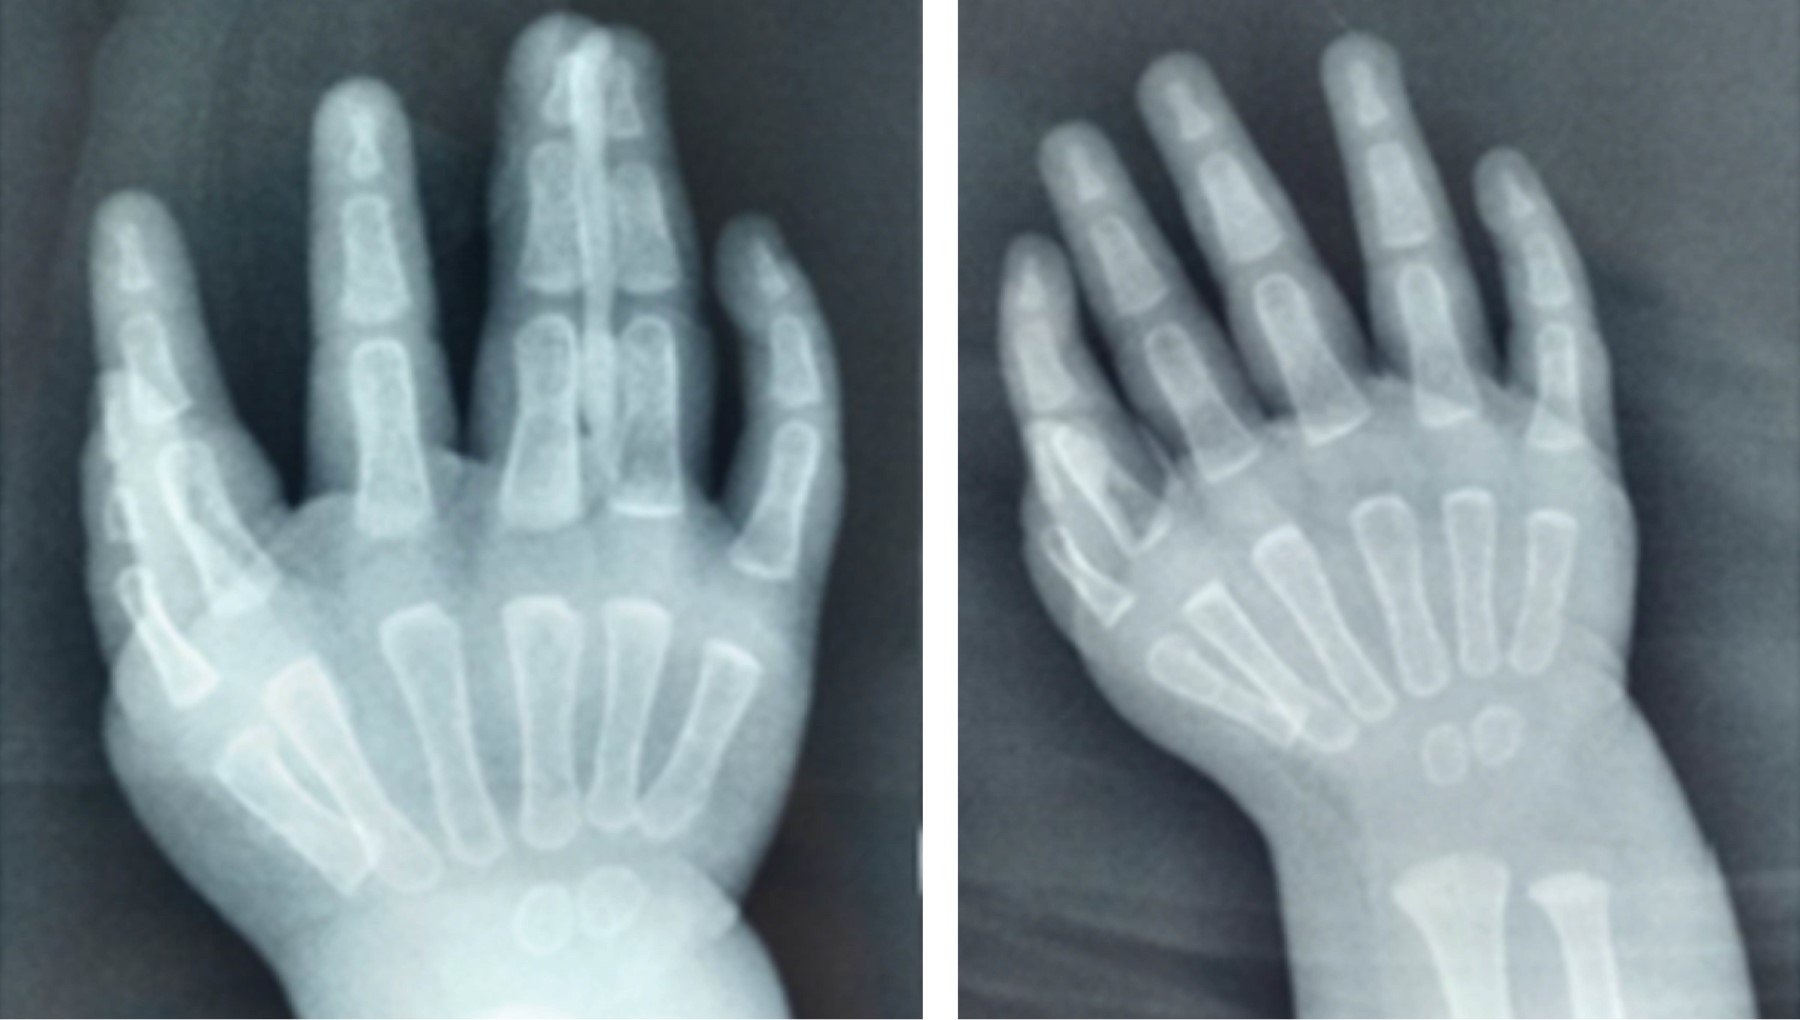

Physical examination presented (Figure 1) both symmetrical thoracic extremities, without shortening nor scapular waist or joint elbows deformities, with posterior hypoplastic forearm musculature, without limitation for prone-supination, both wrists in flexion pose at 40o, limited to 20° extension. The hands with the presence of 6 fingers in both hands in an attitude of flexion, presenting three post-axial triphalangeal fingers and three preaxial, morphologically normal. The examination shows complete mobility arches in shoulders and elbows, without joint instability, with limitation in both wrists (palmar flexion of 75°, dorsal extension 20°, abduction and adduction 5°), the arcs of mobility of the postaxial fingers was normal, and the preaxial fingers showed complete mobility arcs but decreased strength 4/5 on the Daniel’s scale, without pain. Simple X-rays of both hands were requested (Figure 2), finally integrating the diagnosis of bilateral mirror hand syndrome.

Figure 2